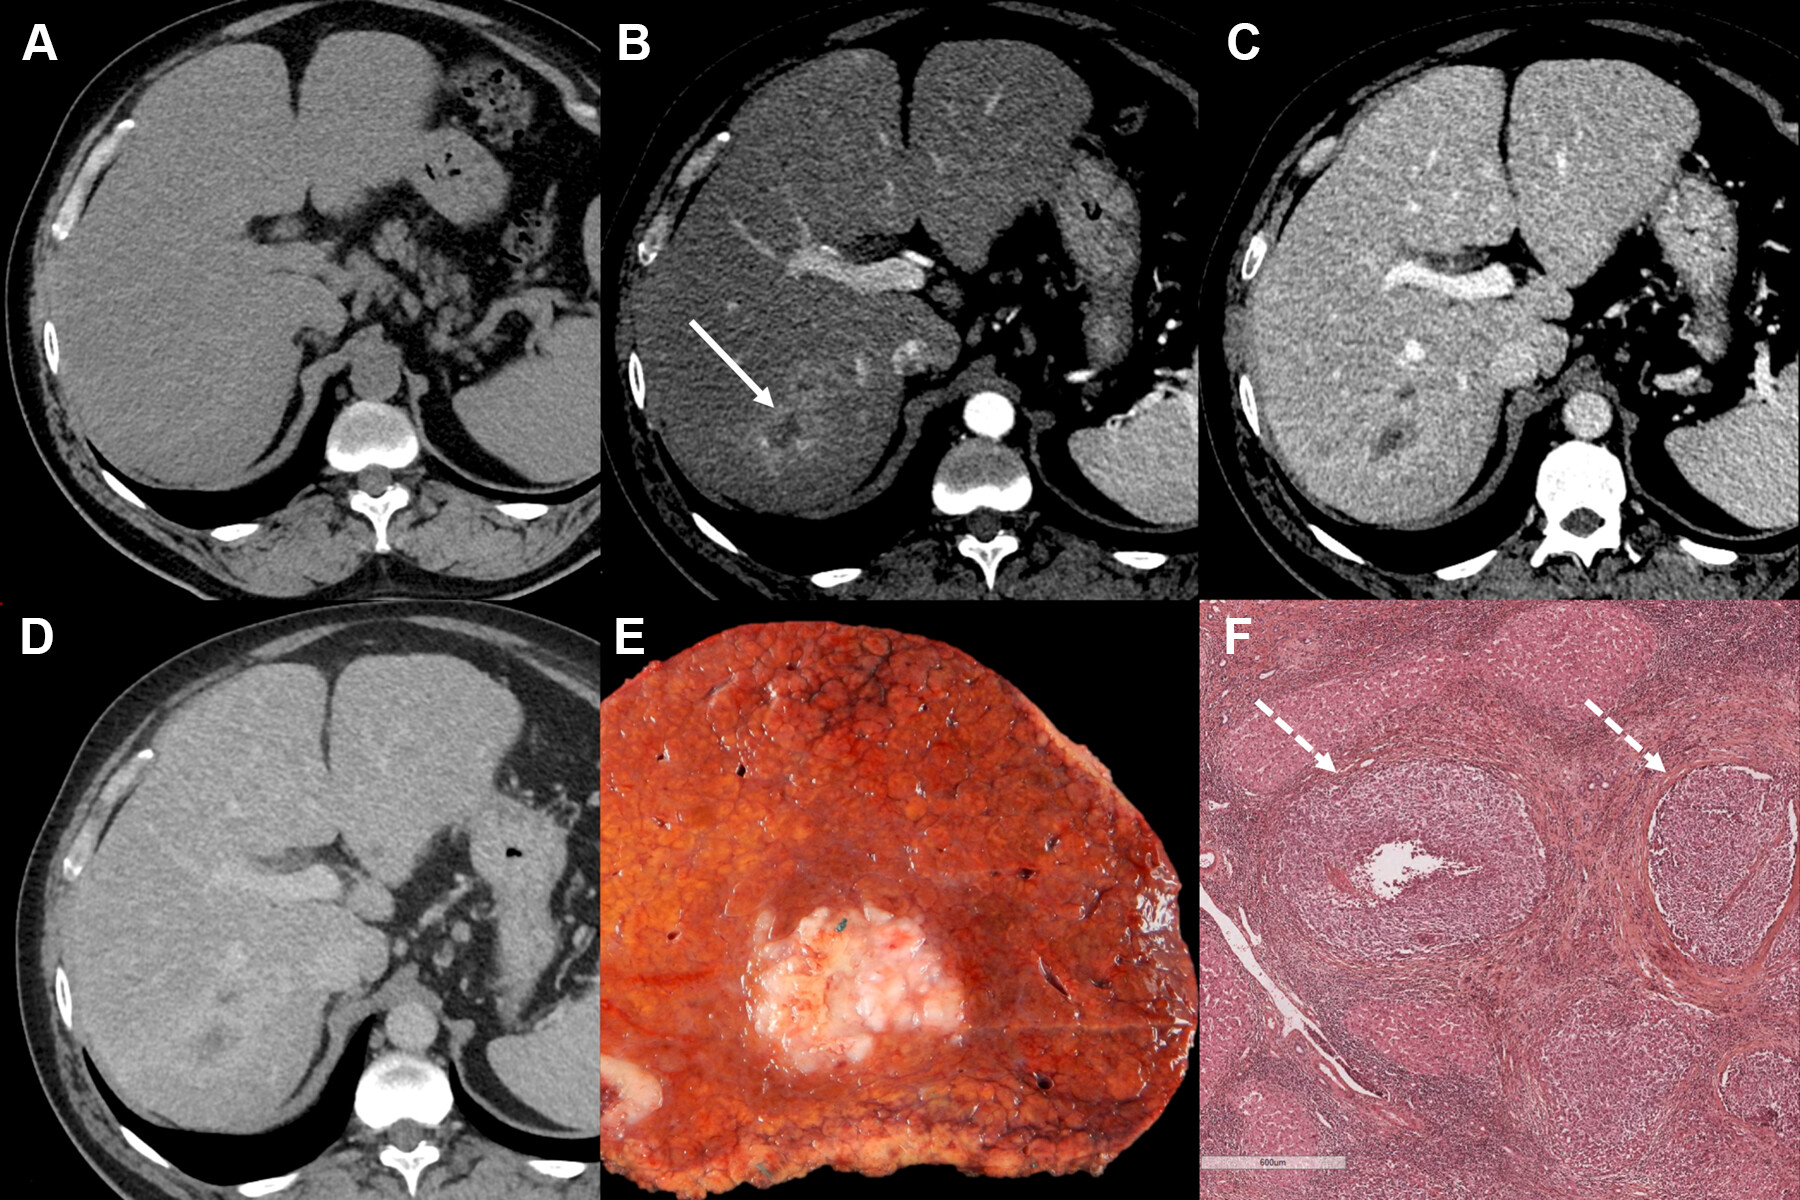

Macrotrabecular-massive HCC is an aggressive variant of the disease that the World Health Organization identified in 2019, according to the investigators. It tends to be diagnosed via preoperative biopsy or postoperative histopathology, but noninvasive alternatives are needed, they noted.

Dual-energy CT is a relatively new CT technology that can characterize tissue beyond conventional CT, and combining radiomic features from DECT exams with deep-learning algorithms shows promise for the diagnosis of rare HCC subtypes, according to Li and colleagues.